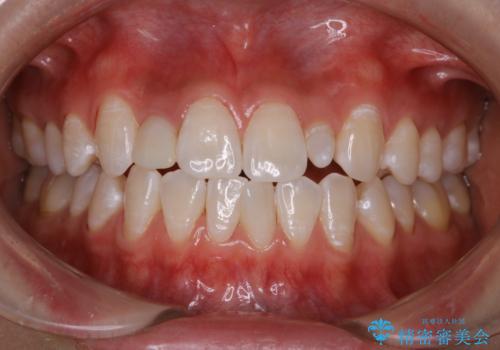

前歯のセラミックを作る前にホワイトニング

- 前歯のセラミッククラウンの型取りの前に、ホワイトニングで全体を白くしたいとのことでした。オフィスホワイトニングのエクセレントコース・トリートメントを行いました。